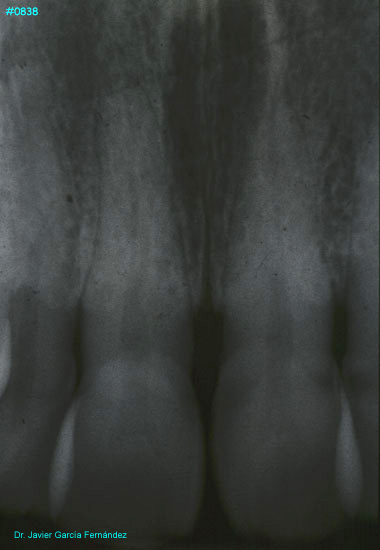

Atlas of Surgical Techniques in Periodontics. Chapter III. Atlas de Técnicas Quirúrgicas en Periodoncia